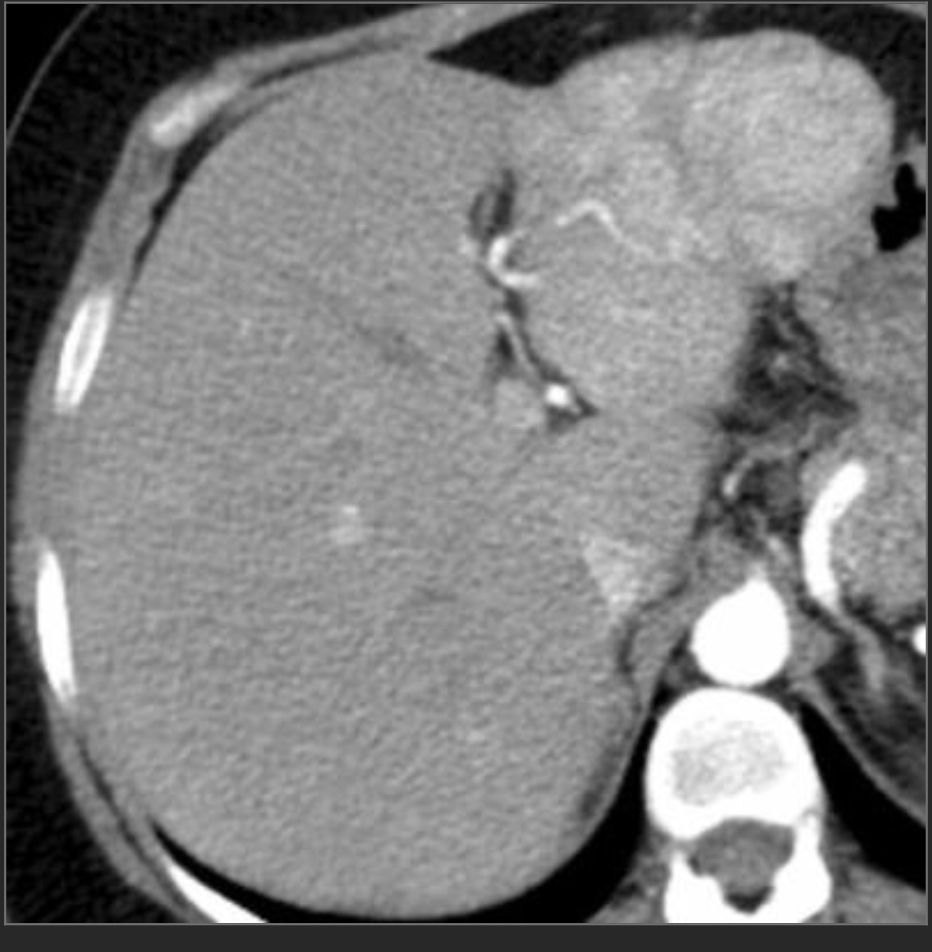

64M w/hx of cirrhosis. P/w acute RUQ pain and this lesion had a pseudoaneurysm

HCC

Hypervascular liver mass in pt w/cirrhosis that spontaneously bleeds is essentially diagnostic of HCC

—> mets dont usually go to cirrhotic livers